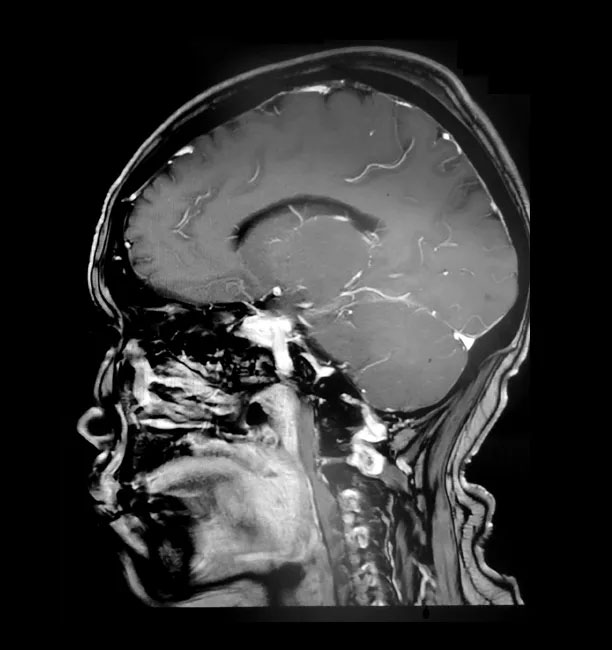

為尋求進一步治療,經(jīng)親友推薦,胡女士慕名前來上海藍十字腦科醫(yī)院。入院后,行頭顱磁共振增強掃描后確認,患者右側(cè)顱底蝶骨嵴-鞍結節(jié)區(qū)實性占位,考慮為腦膜瘤且血供豐富;右側(cè)大腦前動脈A1段與瘤灶貼近。

上海藍十字腦科醫(yī)院神經(jīng)外科主任沈建康教授指出,患者的腦腫瘤直徑約3厘米,只有“鴿子蛋”大小,體積并不大。但蝶骨嵴腦膜瘤由于位置比較特殊,腫瘤有可能和血管神經(jīng)粘連緊密,手術難度和風險都很大。如果沒有做到全切除,腫瘤易復發(fā),可能需要再次手術;術中若損傷瘤體周圍神經(jīng)血管,則可能導致患者殘疾,甚至危及生命。

通過蔡司顯微鏡(雙熒光)下可見,患者蝶骨嵴內(nèi)側(cè)硬腦膜下有淡紅色腫物,血供豐富。腫物大小約2.5cm*2.5cm*1.5cm,腫瘤與額葉底面腦組織粘連,并有較多血管溝通。沈教授聚精會神,抽絲剝繭地自蝶骨嵴位置基底部將腫物從硬腦膜分離。在鏡下保護好視神經(jīng)和頸內(nèi)動脈、大腦中動脈、大腦前動脈等大血管,“螞蟻搬家”般將只有“鴿子蛋”大小的腫物一點一點逐步切除。整臺手術歷時近5個小時,患者術中失血約100毫升,未進行輸血,安返監(jiān)護室后進一步觀察。經(jīng)病理檢查,該腫瘤確診為腦膜瘤。